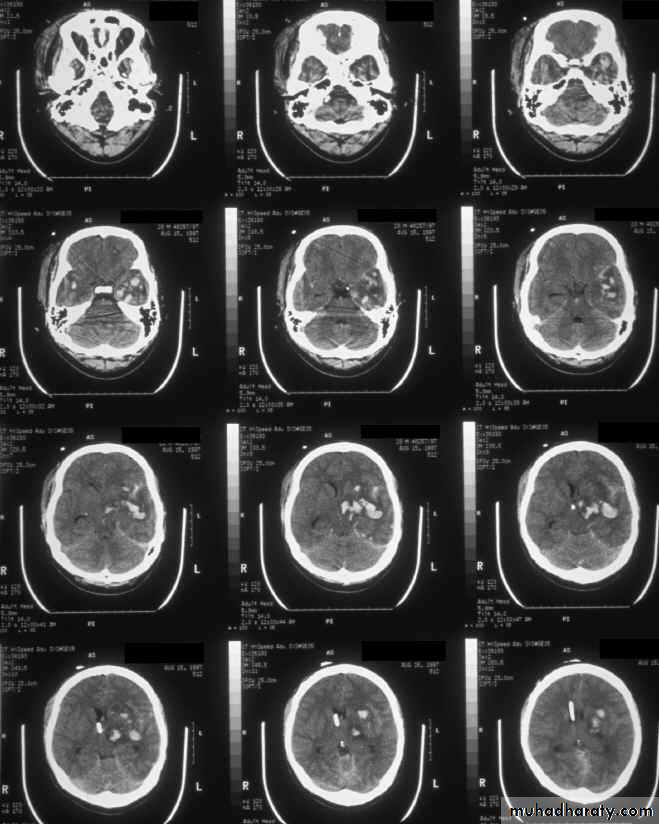

c. Intracerebral Haematoma

This is the least common of traumatic haematoma.

They are due to areas of traumatic contusion coalescing into a contusional haematoma.

Disrupted cerebral tissue release thromboplastins that potentiate haemorrhage.

CT scan: appear as hyperdence lesions with associated mass effect and midline shift.

Large intracerebral haematomas should be evacuated unless the patient’s neurological state is improving.

Small inracerebral haematomas may not require removal, but be aware that they can expand.